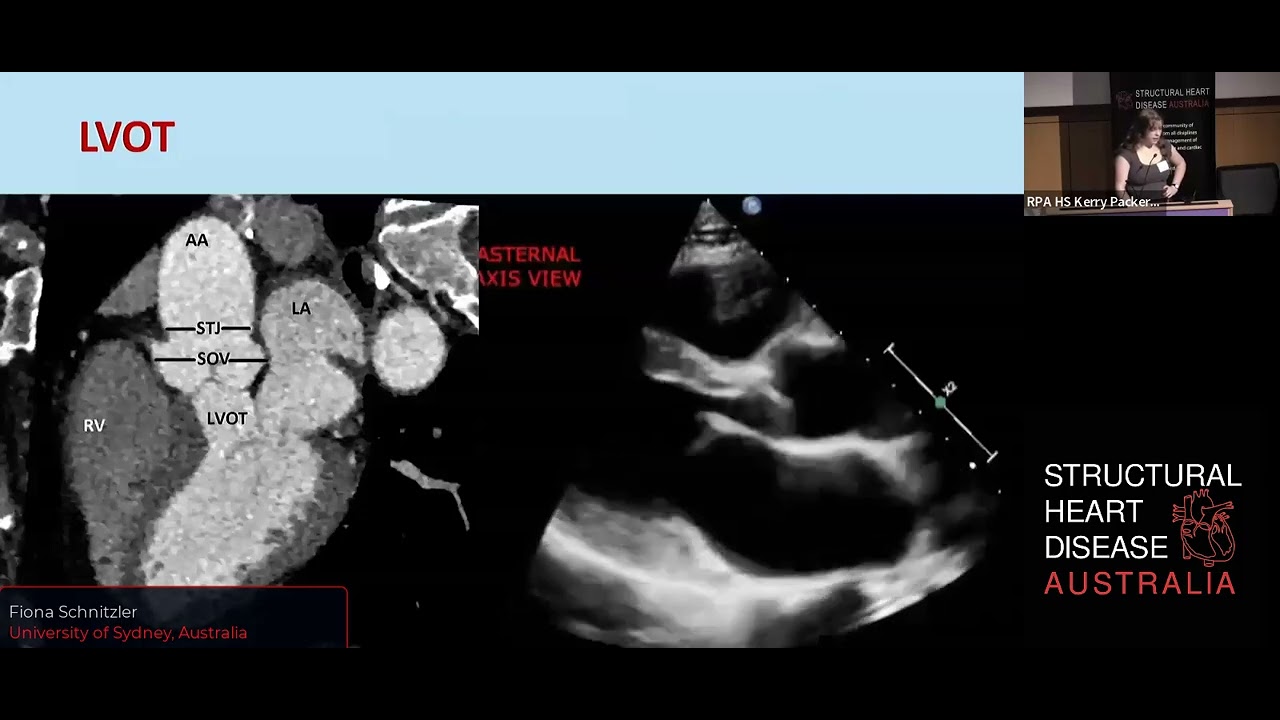

Aortic Valve Anatomy Fiona schnitzler, medical student descibes the anatomy of the aortic valve in aosrtic stenosis more. 3rd year medical student fiona schnitzler describes aortic valve mechanics, aortic stenosis, and aortic valve leaflets in relevance to mitral mechanics. this is a presentation by fiona, a 3rd year medical student, about the anatomy of the aortic valve.

Ventricular Valve Anatomy Aortic Ventricular Valve Duzns Anatomy of the aortic valve dr fiona schnitzler structural heart disease australia • 477 views • 6 months ago. Anatomy of the aortic valve fiona schnitzler 3rd year medical student fiona schnitzler describes aortic valve mechanics, aortic stenosis, and ao…. Step by step – aortic, mitral and tricuspid imaging guidelines for valve implants. The aortic valve is a key orienting structure for the echocardiographer during an intraoperative transesophageal echocardiography exam. its distinctive 3 leaflet, inverted "y" or mercedes benz logo type structure provides a marker through which other cardiac structures can be determined.

Back To The Basics Aortic Valve Anatomy Cardioserv Step by step – aortic, mitral and tricuspid imaging guidelines for valve implants. The aortic valve is a key orienting structure for the echocardiographer during an intraoperative transesophageal echocardiography exam. its distinctive 3 leaflet, inverted "y" or mercedes benz logo type structure provides a marker through which other cardiac structures can be determined. Knowing the basic anatomy of the aortic valve allows us to better evaluate and diagnose patients with pathology. this blog provides the necessary steps to understanding, evaluating and measuring the structure that make up the aortic valve. The aortic valve is typically made up of three membranes (cusps) made up mainly of collagen; the valve is placed on a muscle ring and connected to the heart wall. This review demonstrates the inherent elegance coupled with complexity of the aortic valve apparatus (ava). understanding this could have important clinical and translational implications in optimizing the management of patients with aortic valve disease to enhance longevity and quality of life. Your aortic valve is one of your four heart valves. it opens when blood flows from the left side of your heart to your aorta.